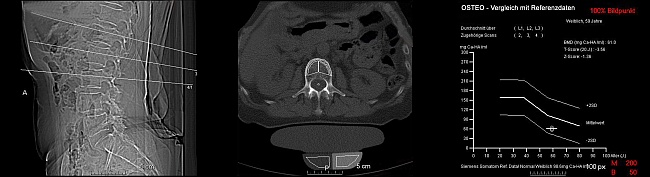

Funktionsweise der Knochendichtemessung (Osteodensitometrie)

Nach einem Orientierungsscout werden Schnitte durch den 1., 2. und 3. Lendenwirbelkörper (LWK) gelegt und zu einem Standardphantom korreliert. Es werden trabekuläre und kortikale Dichtewerte mittels CT gemessen.

Hieraus ergibt sich die Knochendichte (BMD) der gemessenen Wirbelkörper.